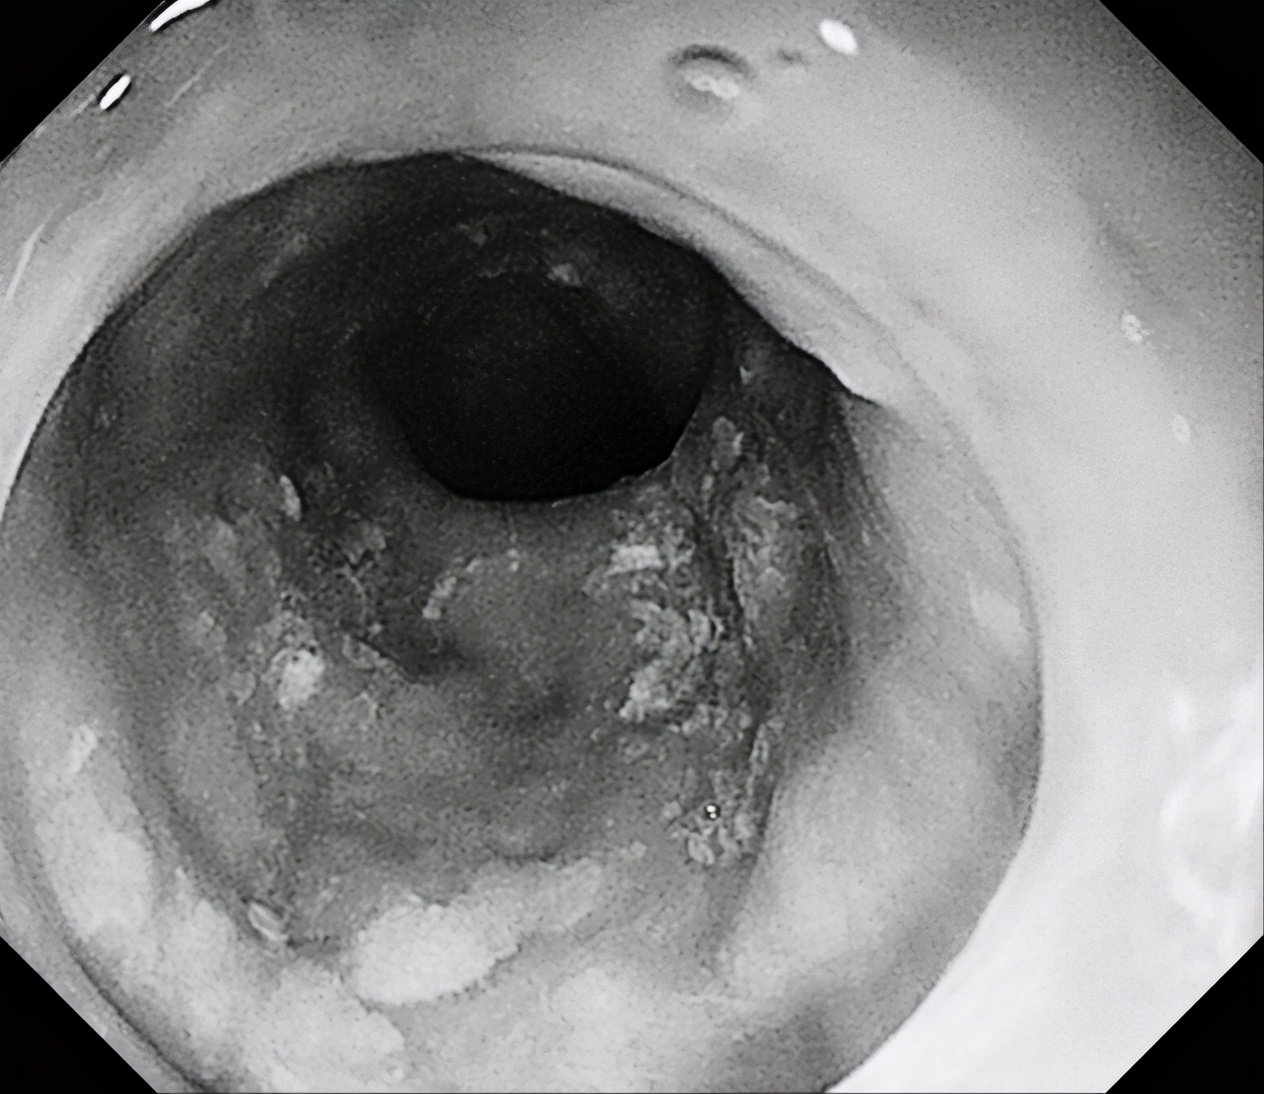

1月6日下午,消化内镜中心张蓉副主任医师为一名患者行胃镜检查时,发现食管中下段黏膜粗糙,覆不均匀少许白苔,粘膜微血管增粗紊乱,行NBI观察及卢戈氏碘染色后发现患者病变呈全周型。

经充分与患者及家属沟通后,患者家属选择外科手术。